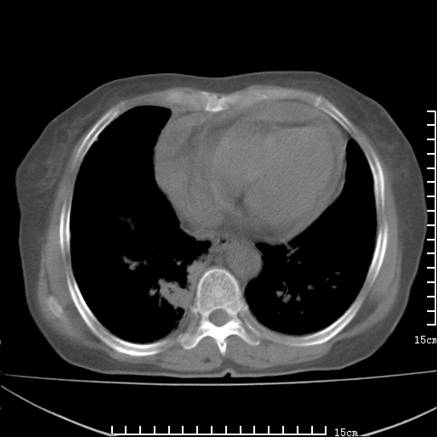

女,王某,58岁,咳嗽三个月余,基层医院二个月前诊为肺结核,用抗结核药二个月无明显疗效。

心包积液致肺瘀血.右侧周围型肺癌伴肺内转移,中间裂积液,叶间胸膜肥厚.右上肺大泡,右侧胸膜肥厚.

双肺继发型tb,心功能不全并肺淤血、心包、双侧叶间裂积液,肺大泡,右下胸膜肥厚钙化。